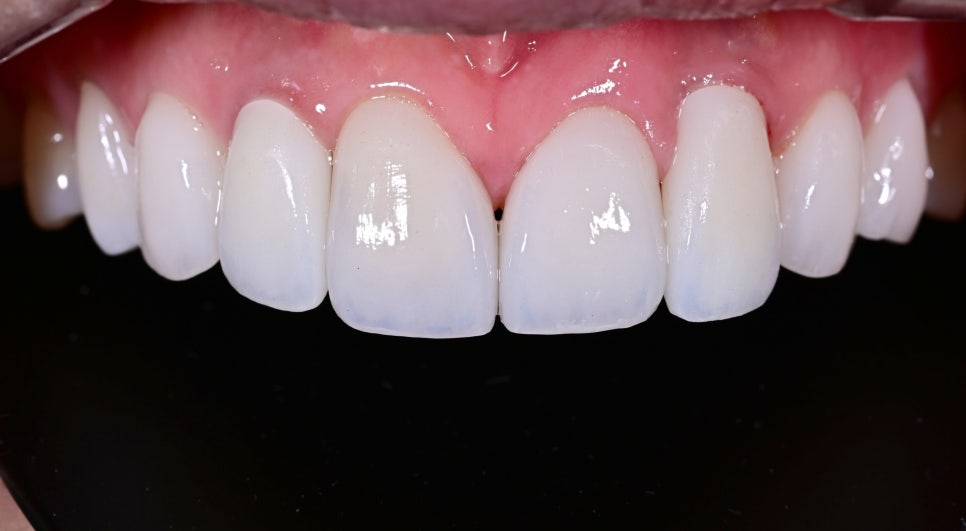

- 오브제로 라미네이트를 통한 전반적인 심미 조화 개선

임플란트만 단독으로 수정하면 오히려 주변 자연치와의 차이가 더 도드라질 수 있기 때문에, 전체 앞니 라인을 고려하여 오브제로 라미네이트를 함께 진행했습니다.

오브제로 라미네이트는 단순히 치아를 하얗게 보이게 하는 것에 그치지 않고, 개개인 얼굴과 미소선, 기존 치아의 특징을 반영하여 보다 자연스럽고 세련된 인상을 만드는 데 강점이 있습니다.

기존에는 임플란트 부위가 주변 치아와 미묘하게 다르게 보여 앞니 전체의 통일감을 해치고 있었지만, 치료 후에는 앞니의 색감과 형태, 비율이 훨씬 부드럽게 연결되면서 전체 인상이 한층 정돈되고 자연스러워졌습니다.

또한 너무 차갑거나 인위적인 흰색이 아니라 환자분 이미지에 어울리는 깨끗하고 고급스러운 화이트 톤으로 완성되어 웃을 때의 분위기 자체가 훨씬 밝아졌습니다.